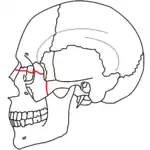

Le Fort I fractures

At the beginning of the 20th century, René Le Fort mapped typical locations for facial fractures; these are now known as Le Fort I, II, and III fractures (right).[7] Le Fort I fractures, also called Guérin or horizontal maxillary fractures,[14] involve the maxilla, separating it from the palate.[15] Le Fort II fractures, also called pyramidal fractures of the maxilla,[16] cross the nasal bones and the orbital rim.[15] Le Fort III fractures, also called craniofacial disjunction and transverse facial fractures,[17] cross the front of the maxilla and involve the lacrimal bone, the lamina papyracea, and the orbital floor, and often involve the ethmoid bone,[15] are the most serious.[18] Le Fort fractures, which account for 10–20% of facial fractures, are often associated with other serious injuries.[15] Le Fort made his classifications based on work with cadaver skulls, and the classification system has been criticized as imprecise and simplistic since most midface fractures involve a combination of Le Fort fractures.[15] Although most facial fractures do not follow the patterns described by Le Fort precisely, the system is still used to categorize injuries.[5]